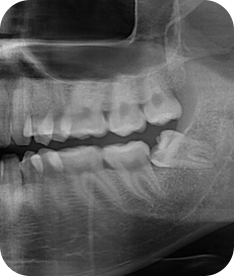

사랑니 발치

청담네오플란트는 3D CT 촬영 후 전문의료진들의 정확한 분석으로 안전하게 사랑니를 발치합니다.

청담네오플란트치과 사랑니 발치 프로세스

01. CT 촬영

안전하고 통증을 최소화한 발치를 위해 3차원 정밀 분석을 합니다.

02. 정확한 분석

사랑니의 크기와 방향, 깊이, 뿌리 상태 등과 구강검진을 실시합니다.